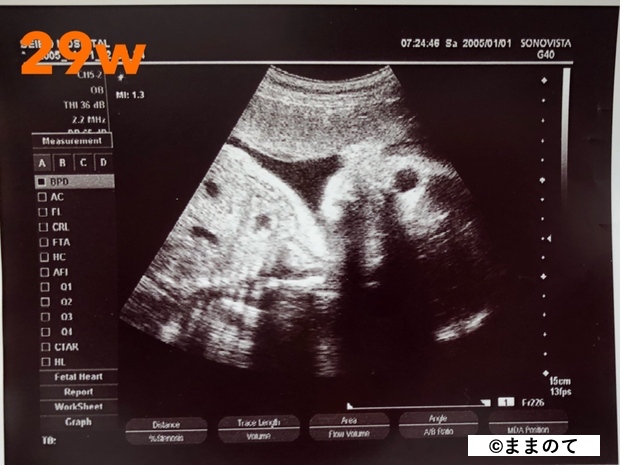

妊娠8ヶ月(28・29・30・31週)

脂肪がついてきて、赤ちゃんがふっくらとしてきます。子宮の中では収まる場所が定まってきます。手足を丸めている様子がうかがえるかもしれません。

身長は約40cm、体重は1,500~1,800gです。3Dエコーや4Dエコーでは全身は映りませんが、赤ちゃんらしい表情を見られる時期です。